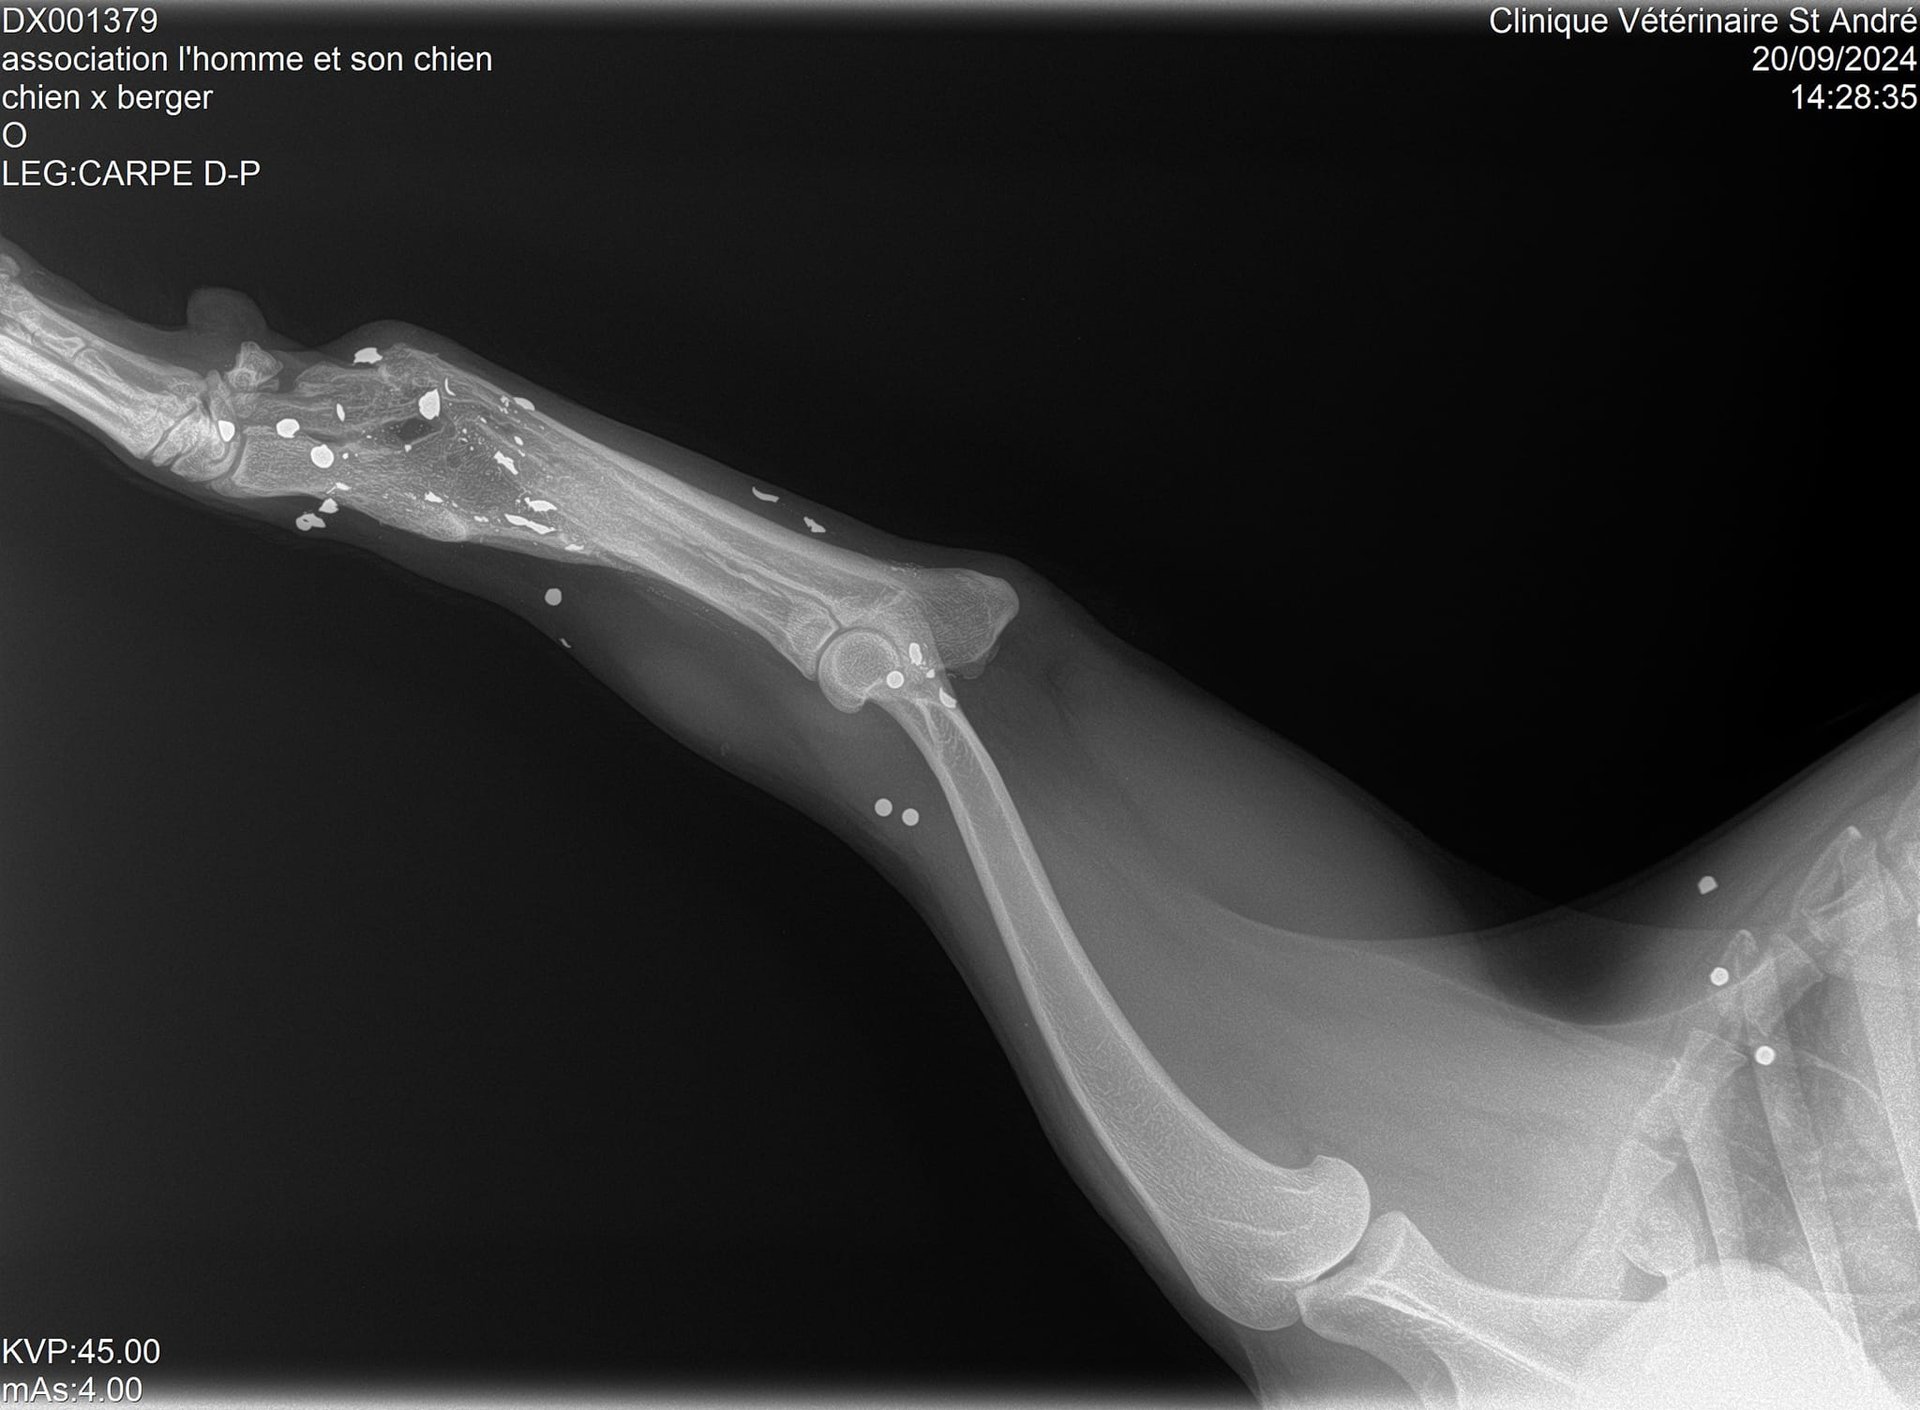

Sa patte avant gauche, criblée de balles, est détruite et, malgré ça, il est obligé de s'en servir car il ne pose pas toujours sa patte arrière droite…

Vous allez halluciner en voyant ses radios !